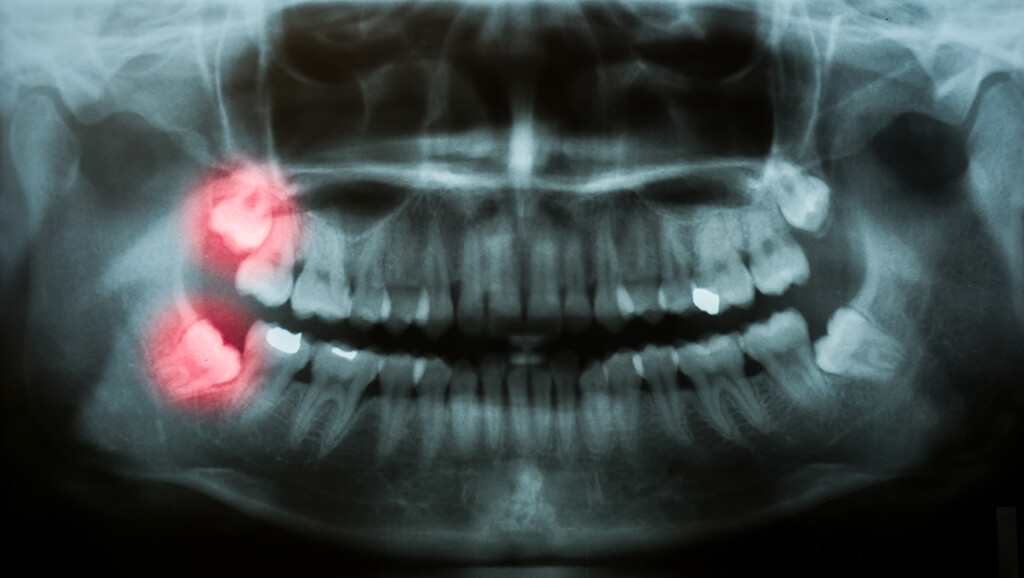

Impacted Wisdom Tooth

One of the most common issues associated with wisdom teeth is impaction. Wisdom teeth that don't have enough space to grow properly can emerge at awkward angles, and become stuck underneath the gums or even the jaw bone. This can cause pain, infection, and damage to nearby teeth. The type of impacted wisdom tooth you have will affect the surgical extraction procedure that will be used, and whether a simple tooth extraction can be performed.

Soft tissue impaction occurs when the tooth cannot emerge fully from under the gum, creating a gum flap that is a home for bacteria.

A partial bony impaction occurs when the tooth is not able to completely emerge from the bone, so it is stuck underneath the gum, and partially under the bone. This can lead to infection and cysts.

With a complete bony impaction, the tooth is unable to break through the surface of the bone at all. This requires the most complex surgical procedure for removal.